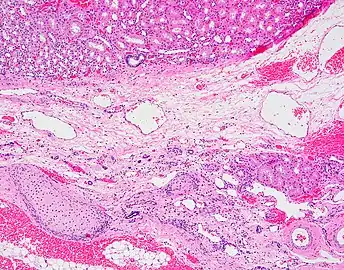

Мікрофотографія (рос. микрофотография, англ. photomicrography, нім. Mikrophotografie) — техніка фотографування малих об'єктів, здебільшого за допомогою мікроскопів. Широко використовують з метою наукового вивчення об'єктів шляхом значного збільшення їх зображень (наприклад, аншліфів вугілля, мінералів, біологічних клітин та тканин).

Також слово мікрофотографія широко використовують для визначення фотографій (знімків), створених з використанням мікроскопа.